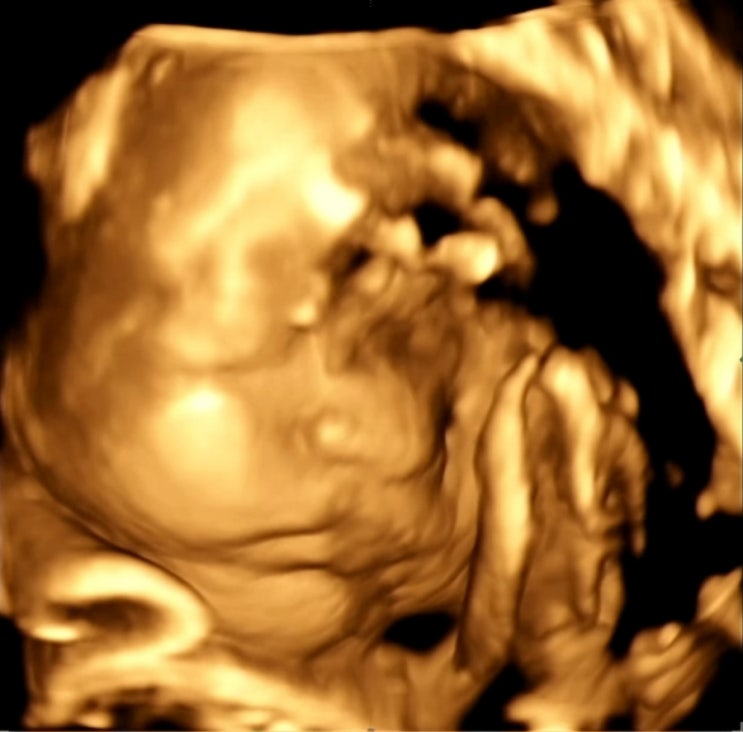

입체초음파 시기 코 첫째랑 비교 28주 사진 실패

안녕하세요. yeon입니다. 벌써 28주차 임산부가 되었어요. 이젠 중기가 지나 후기 임산부가 된 저는 요즘 ...